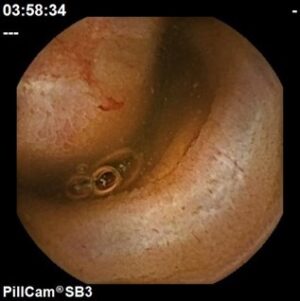

Úlcera com vaso visível intestino delgado

Hospital Senhora da Oliveira (Guimarães)